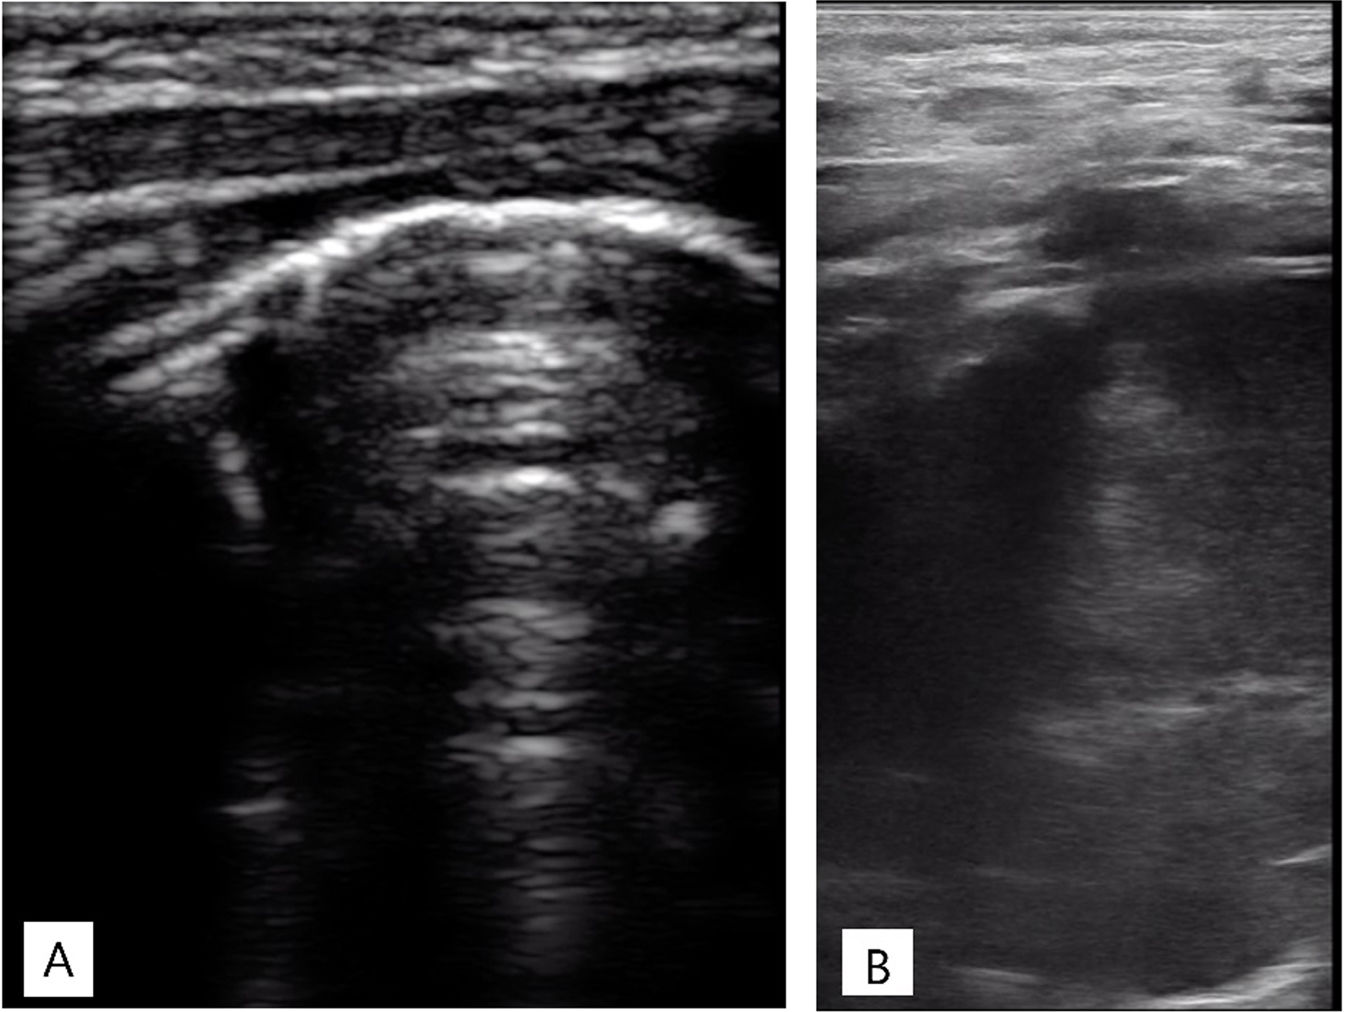

La radiografía de tórax mostraba una opacidad completa en el lóbulo superior derecho (fig. 1), mientras que las ecografías pulmonares seriadas eran normales (fig. 2A). La ecografía torácica realizada desde el plano supraclavicular mostraba una consolidación bien definida sugestiva de masa torácica (fig. 2B y vídeo 1) que se evidencia en la TAC (fig. 3). La biopsia confirma el diagnóstico de neuroblastoma congénito.

Ecografía torácica realizada con sonda lineal de alta frecuencia. A)Plano longitudinal a nivel de campo pulmonar anterior, superior derecho. Adecuado deslizamiento pleural, buena aireación en todos los campos pulmonares, con patrón de líneas A y puntuación de Brat de 0 puntos. B)Plano supraclavicular derecho. Consolidación sin broncograma aéreo ni captación en el doppler con borde profundo bien definido y redondeado de 6cm de diámetro máximo.